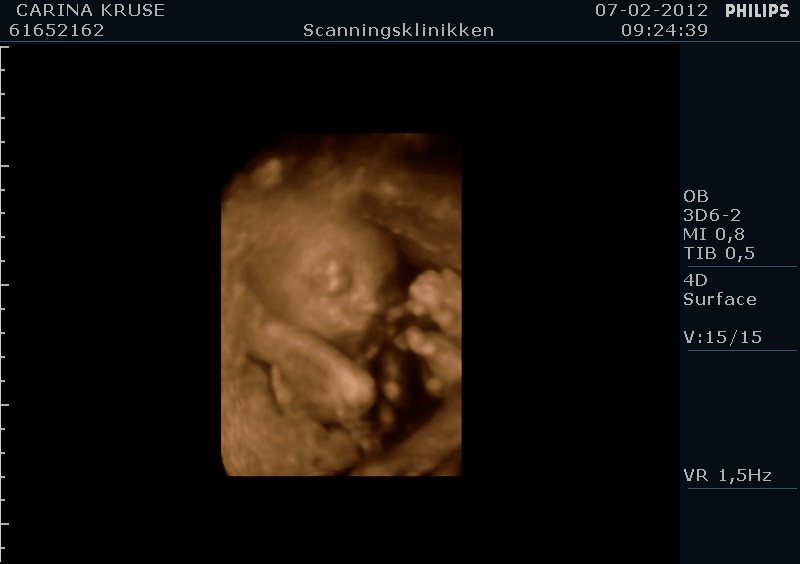

Og sikke en oplevelse, vores lille Filucca lå dog bare og sov som en sten hehe, men vi fik da lige et enkelt gab inden vi sluttede

Her er lige et par billeder af vores lille babypige